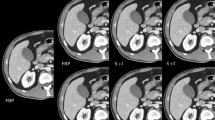

In protocol B, the mean image noise decreased as the monochromatic energy level increased from 40 to 70 keV. Mean image noise for protocol A was 17.00 HU ± 4.38 in AP and 17.29 HU ± 4.26 in PVP, respectively, significantly lower than those for the energy levels at 40 keV (23.37 HU ± 5.21 and 22.51HU ± 4.23), similar to those at 50 keV (16.98 HU ± 4.07, P =0.985 and 16.85 HU ± 3.84, P =0.078), higher than those at 60 keV (11.83 HU ± 2.98 and 12.06 HU ± 2.43) and 70 keV (11.25 HU ± 3.16 and 11.50 HU ± 2.97), an average increase of 44 % and 43 % for 60 keV, 51 % and 50 % for 70 keV, respectively (P < 0.001 for each comparison with statistical difference) (Fig. 1).

Transverse contrast-enhanced conventional CT images (a for AP, f for PVP) with 120 kVp, 90 mL contrast agent and FBP in a 57-year-old man with BMI of 25.71 kg/m2 and monochromatic images (b-e for AP and g-j for PVP) with spectral imaging, 43 mL contrast agent and ASIR in a 55-year-old man with BMI of 24.44 kg/m2. The overall image qualities for the images at 120 kVp were similar to that at 40 keV, lower than those at 50 keV and 60 keV, and higher than that at 70 keV

The image quality scores of the two protocols and the level of inter-observer agreement are shown in Table 4. All image quality scores, irrespective of the protocol, were equal to or greater than 2 which indicate an acceptable overall image quality. Compared with protocol A , the analyses of the subjective readers’ rankings were significantly higher in protocol B at 50 keV and 60 keV with regard to overall image quality (P < 0.001 for each comparison), similar at 50 keV, but lower at 60 keV with respect to image noise (P < 0.001), higher at 50 keV (P < 0.001), but similar at 60 keV with respect to small vascular structure visibility and abdominal organ enhancement. The energy level at 40 keV in protocol B showed higher small vascular structure visibility (P < 0.001), abdominal organ enhancement (P <0.001), and image noise (P =0.004 for AP; P <0.001 for PVP ), but similar overall image quality as compared with protocol A. Lower overall image qualities were observed for the energy level at 70 keV in protocol B than that in protocol A.